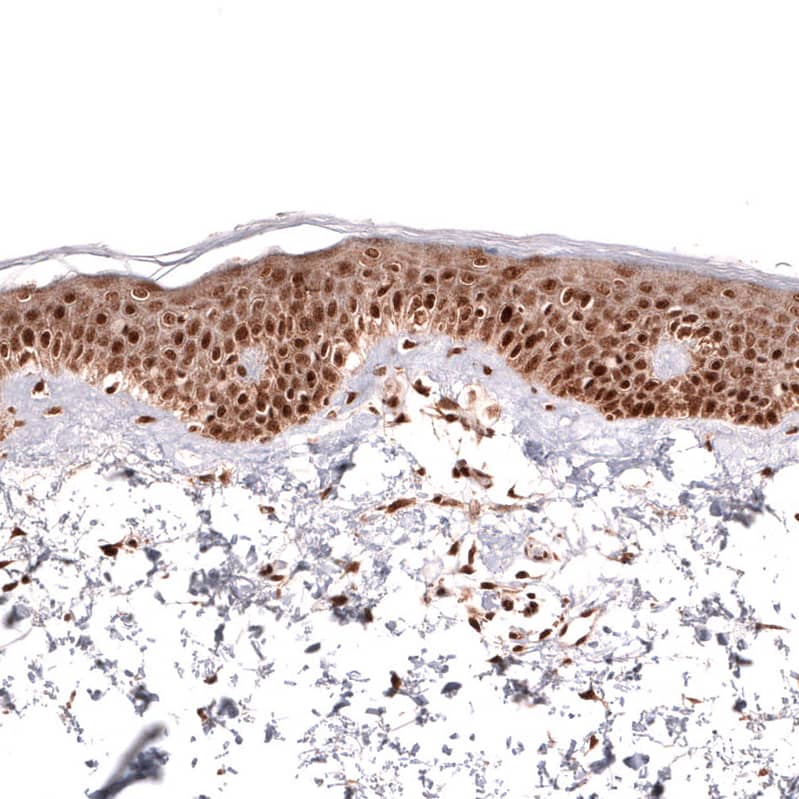

Staining of human skin shows strong nuclear positivity in squamous epithelial cells.